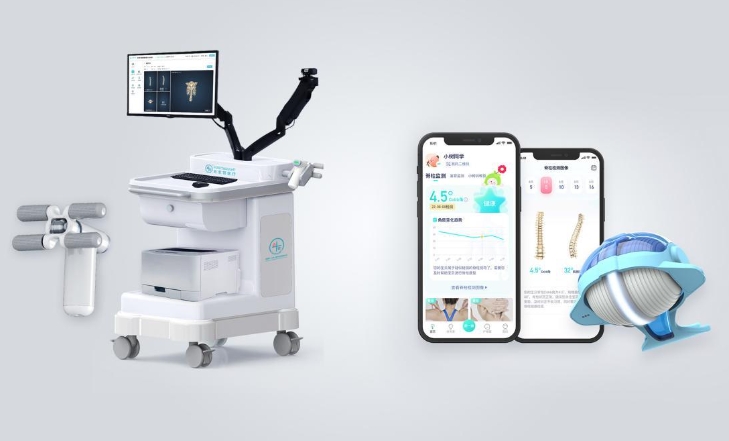

Die Bequemlichkeit und Innovation von Handheld-Screening auf Skoliose - Voraussicht

Im Rahmen der laufenden Bemühungen um eine frühzeitige Erkennung und Intervention im Bereich der Wirbelsäulengesundheit erweist sich das Handheld Screening for Scoliosis als revolutionäres und äußerst praktisches Instrument, insbesondere für Massenuntersuchungen im schulischen Umfeld. Dieses tragbare Gerät wurde entwickelt, um die Landschaft der Skoliosebeurteilung zu verändern, indem es eine praktische und zugängliche Lösung zur effizienten Erkennung von Wirbelsäulenunregelmäßigkeiten bei einer großen Anzahl von Schülern bietet.

Nicht-radiometrischer und patientenfreundlicher Ansatz:

Eines der herausragenden Merkmale des Handheld Screening for Scoliosis ist seine nicht-radiometrische Methode. Traditionell werden Skolioseuntersuchungen häufig mit Röntgenstrahlen durchgeführt, wodurch Personen, insbesondere Heranwachsende, ionisierender Strahlung ausgesetzt werden. Im Gegensatz dazu wird bei diesem Handgerät eine innovative Technologie eingesetzt, die radiometrische Messungen überflüssig macht. Dadurch wird nicht nur die Sicherheit der untersuchten Personen gewährleistet, sondern auch ein patientenfreundlicher Ansatz gefördert, der besonders in Schulen wichtig ist, in denen ein breites Spektrum an Altersgruppen und gesundheitlichen Aspekten vertreten ist.

Tragbarkeit und Benutzerfreundlichkeit:

Die Tragbarkeit und Benutzerfreundlichkeit dieses Screening-Tools ist ein entscheidender Faktor für die Durchführung von Reihenuntersuchungen. Im Gegensatz zu herkömmlichen Röntgengeräten, die schwerfällig sein können und spezielle Einstellungen erfordern, ermöglicht das tragbare Gerät dem Gesundheitspersonal, Screenings flexibel und effizient durchzuführen. Sein benutzerfreundliches Design macht es für eine Vielzahl von Gesundheitsdienstleistern zugänglich, einschließlich Schulkrankenschwestern oder medizinischen Besuchsteams, und trägt so zur nahtlosen Integration von Skoliose-Screenings in die schulische Gesundheitsroutine bei.

Intelligente Lichtsensortechnologie:

Das Herzstück des Handheld Screening for Scoliosis ist seine innovative Smart Light Sensing Technology. Diese bahnbrechende Funktion nutzt die dynamische Erfassung kleiner Winkelgeschwindigkeitsänderungen mit MEMS-Sensoren (Micro-Electro-Mechanical Systems). Die MEMS-Sensoren ermöglichen eine präzise Messung der Wirbelsäulenverkrümmung in Echtzeit, ohne dass herkömmliche Röntgenmethoden erforderlich sind. Diese fortschrittliche Technologie verbessert nicht nur die Genauigkeit der Bewertungen, sondern rationalisiert auch den Screening-Prozess und macht ihn effizient und effektiv.

Präzise Geländescanner-Technologie:

Ein weiteres herausragendes Merkmal, das zur Bequemlichkeit von Massenscreenings beiträgt, ist die in das Handheld-Gerät integrierte Accurate Terrain Scanning Technology. Diese Technologie passt sich an die Geschwindigkeit und die Bewegungen des Bedieners an und gewährleistet die Erfassung der besten Geländedaten für die Skoliosebeurteilung. Das Gerät passt seine Scan-Parameter auf intelligente Weise an die Bewegungen des Anwenders an und ermöglicht so eine individuellere und zuverlässigere Beurteilung der Wirbelsäulenverkrümmung. Die Verarbeitung von Informationen auf mehreren Ebenen und in mehreren Räumen verbessert die Vollständigkeit der erfassten Daten und trägt so zur Präzision der Ergebnisse des Skoliose-Screenings bei.

Gleichzeitige Erfassung von orthopädischen und lateralen Daten:

Die Effizienz wird durch die Fähigkeit des Geräts zur gleichzeitigen Erfassung orthopädischer und lateraler Daten weiter maximiert. Diese doppelte Datenerfassung in Echtzeit ermöglicht einen ganzheitlichen Blick auf die Ausrichtung der Wirbelsäule. Die Möglichkeit, sowohl orthopädische als auch laterale Daten in einem nahtlosen Prozess zu erfassen, beschleunigt nicht nur das Screening, sondern bietet dem medizinischen Fachpersonal auch umfassende Einblicke, die zu einer fundierten Entscheidungsfindung beitragen.

Zugängliches Screening im schulischen Umfeld:

Die Bequemlichkeit des Handheld Screening for Scoliosis geht über seine technischen Merkmale hinaus. Sein tragbares und benutzerfreundliches Design ermöglicht die Durchführung von Untersuchungen direkt in der Schule. Diese Zugänglichkeit ist ein entscheidender Vorteil, da die Schüler für routinemäßige Skoliose-Screenings nicht mehr zu externen Gesundheitseinrichtungen fahren müssen. Die Möglichkeit, das Screening-Tool in die Schulen zu bringen, erleichtert einen integrativeren und proaktiveren Ansatz für die Gesundheit der Wirbelsäule und stellt sicher, dass eine größere Anzahl von Schülern von regelmäßigen Untersuchungen profitieren kann.

Stärkung der Frühintervention:

Durch die Erleichterung von Massenscreenings in Schulen wird das Handheld Screening for Scoliosis zu einem leistungsfähigen Instrument für die Förderung von Frühinterventionsstrategien. Die frühzeitige Erkennung von Skoliose ermöglicht eine rechtzeitige Überwachung und bei Bedarf geeignete Interventionen, die ein Fortschreiten der Wirbelsäulenverkrümmung und damit verbundene Komplikationen verhindern können. Die Bequemlichkeit der schulischen Untersuchungen erhöht die Wahrscheinlichkeit, dass mehr Schüler erreicht werden, und fördert eine Kultur des proaktiven Bewusstseins für die Gesundheit der Wirbelsäule.